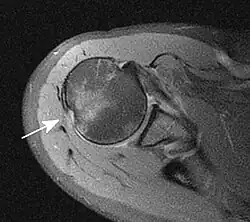

Grundlage ist die Anamnese (Unfallmechanismus) und körperliche Untersuchung (Funktionseinschränkung). Dabei muss insbesondere die Schädigung von Blutgefäßen und Nerven beachtet und dokumentiert werden. Durch Röntgenbilder in verschiedenen Ebenen wird die Diagnose gesichert und eine Fraktur ausgeschlossen. Zum Ausschluss einer Bankart-Läsion (s. u.) kann eine MRT-Aufnahme angefertigt werden.

Als Hill-Sachs-Delle bezeichnet man eine Knochenimpression am Humeruskopf. Sie kann durch eine Unterfütterung mit Spongiosa oder eine Drehosteotomie (nach Weber, nur noch selten angewandt) behandelt werden. Unter einer Bankart-Läsion versteht man den Abriss des knorpeligen Labrum glenoidale inferius von der Gelenkpfanne. Daraus kann eine vordere Schulterinstabilität resultieren. Die operative Therapie besteht in einer arthroskopischen Refixierung (Bankart-repair) oder einer Rekonstruktion mittels eines Knochenspans, z. B. in der Technik nach Latarjet. Beide Läsionen sind Risikofaktoren für ein rezidivierendes Auftreten weiterer Luxationen.